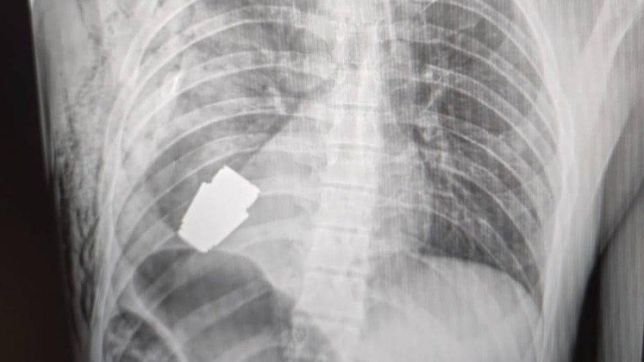

Em sua página no Facebook, o Comando das Forças Médicas das Forças Armadas da Ucrânia compartilhou a imagem de uma radiografia que mostra a granada alojada no peito do soldado.

"A operação foi realizada por um dos cirurgiões mais experientes das Forças Armadas da Ucrânia – major-geral do Serviço Médico, Andrei Verba – sem coagulação elétrica, pois a munição poderia detonar a qualquer momento", escreveu o comando.

A eletrocoagulação é usada em procedimentos cirúrgicos com objetivo de interromper sangramentos, mas por envolver, como o próprio nome diz, ondas elétricas, havia a possibilidade de uma explosão. Ainda segundo a publicação, o "a intervenção cirúrgica foi bem-sucedida, e o militar ferido foi encaminhado para reabilitação e recuperação".